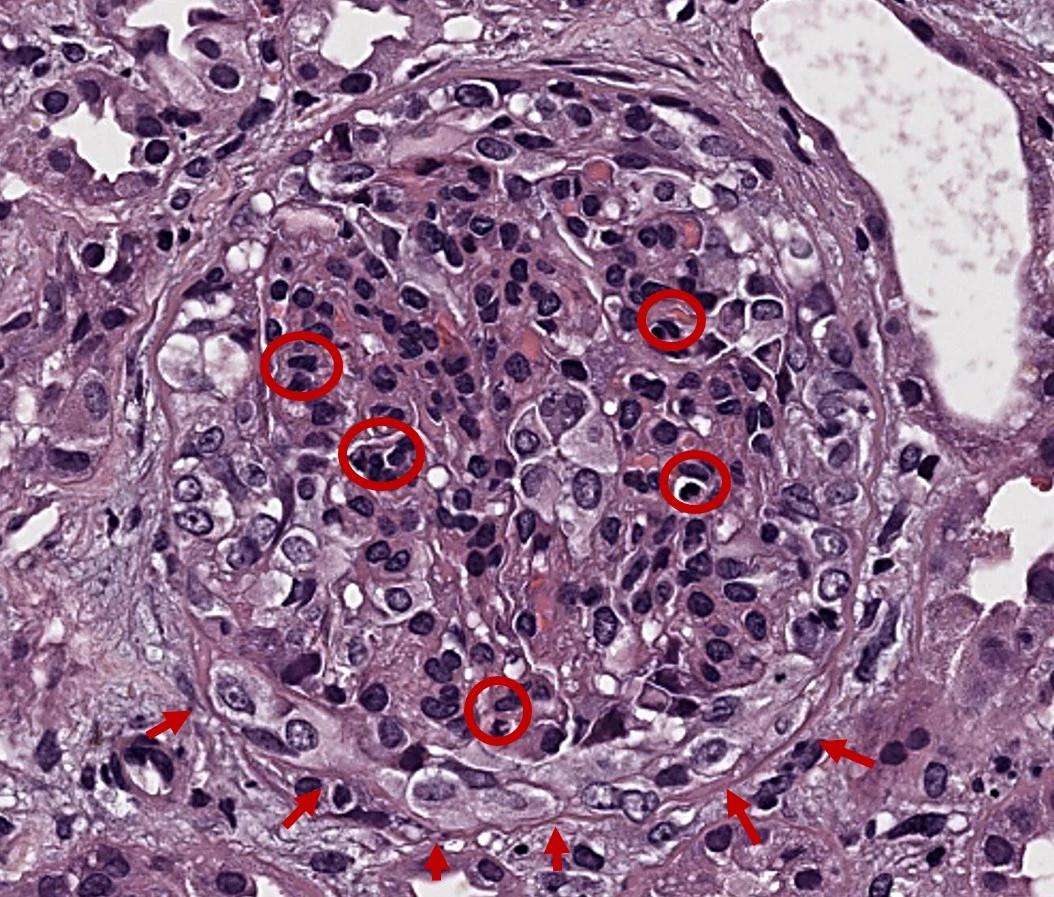

Los patrones de lesión en la microscopía óptica son heterogéneos, dentro de los que se pueden incluir expansión y/o proliferación mesangial (Img. 2), proliferación endocapilar y proliferación extracapilar (Img. 3). También pueden observarse lesiones crónicas, representadas por la glomeruloesclerosis focal y segmentaria, atrofia tubular y/o fibrosis intersticial. La microscopía electrónica muestra depósitos mesangiales (Img. 4) y ayuda al diagnóstico diferencial con otras patologías que cursan con depósito de IgA, como lo son la glomerulonefritis postinfecciosa IgA-dominante («jorobas») y la nefropatía lúpica (inclusiones túbulo-reticulares), entre otras12. Todos estos hallazgos están englobados en la clasificación de Oxford (puntuación MEST-C), permitiendo establecer un índice pronóstico13, unido a la positividad para C4d (Img. 5) que pone de manifiesto la activación de la vía de las lectinas y se ha asociado a peor pronóstico renal14.

H&E con proliferación mesangial mayor de 3 células por área mesangial en Nefropatía IgA

Img. 2. H&E. Glomérulo con proliferación mesangial (>3 células/área mesangial) (O rojo). 40x.

Img. 3. H&E. Glomérulo con proliferación endocapilar global a expensas de polimorfonucleares neutrófilos y monocitos (O rojo) además de proliferación extracapilar con formación de una semiluna celular (→ rojo). 40x.